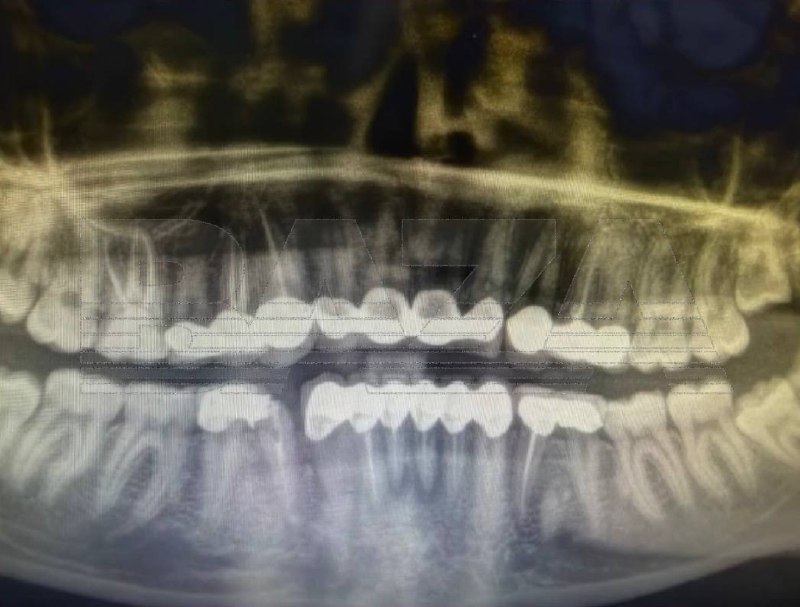

⚡️Россиянка полетела в Турцию за «улыбкой как у Егора Крида», но получила воспаление и сломанные коронки, — СМИ.

Девушка поехала в турецкую клинику ставить виниры, однако во время процедуры ей сильно спилили зубы и фактически установили коронки и мосты. После лечения начались сильные боли и в клинике ей удалили шесть нервов.

Позже воспаление вернулось — в экстренной стоматологии врачи обнаружили инфекцию, удалили ещё несколько нервов и предупредили о риске госпитализации. Одна из коронок также треснула, а новое лечение оценивают примерно в $2000.